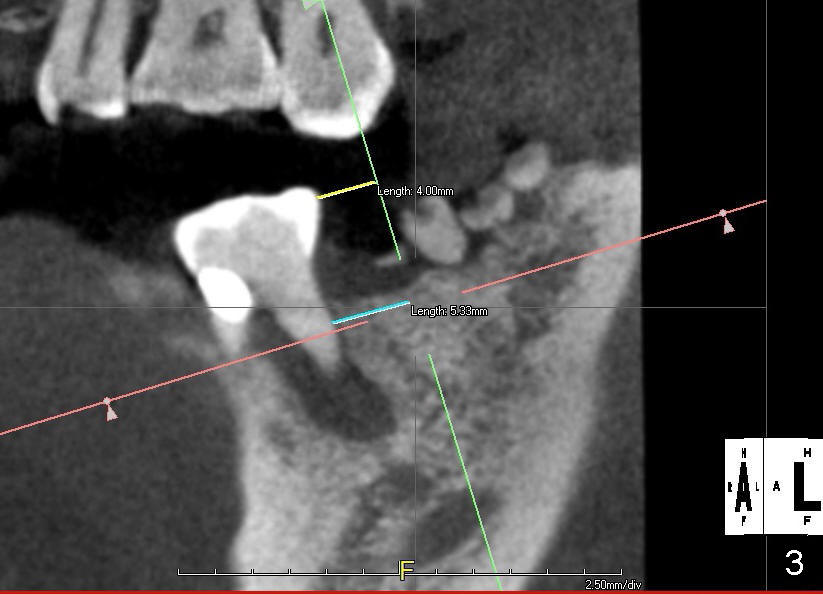

A restoratively oriented design pays attention to occlusion. The center of the 2 mm pilot drill will be 4 mm from the neighboring tooth (Fig.3).

Probably due to long standing edentulism, the buccal plate is atrophic. In order for the future crown (mainly its buccal cusp) to occlude with the lingual cusp (Fig.4 L, functional cusp) of the upper 2nd molar, the coronal end of the bone-level implant should be more buccal than the traditional one (Fig.2), whereas the apical end more lingual. But not too much! The lingual plate should be protected. Place a finger in the submandibular fossa (SF) while making osteotomy.

Root canal therapy has been done for the tooth #19. Before surgery, take a PA using the existing layout to confirm that the apical radiolucency has been reduced or disappeared. After finishing 2 mm pilot drilling at the depth 8 mm, insert a paralleling pin and check the trajectory against the upper opposing tooth. Make necessary adjustment with Linderman bur. Then take PA to check mesiodistal trajectory and proximity to the nerve. Deepen osteotomy to 12 mm (deeper than 11 mm mark). Use reamers for further osteotomy. The autogenous bone will be saved and placed most likely in the buccal aspect when the buccal threads are exposed (Fig.4: red circle). Use collagen dressing (apron-shaped with a hole in the middle, buccal portion wider). Use a 5.2 (or 6.2 mm) healing abutment to hold the dressing in place. From Fig.4, can you guess what length and cuff should be chosen? How is the result?